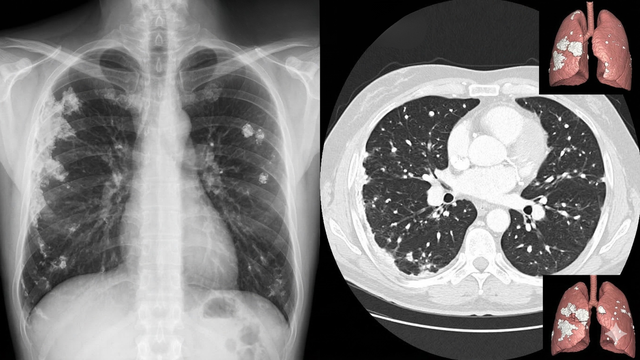

canxi hoá